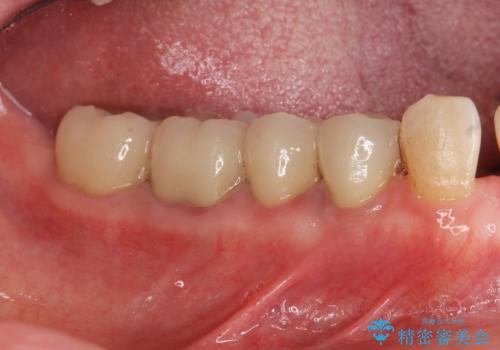

- 27万円(仮歯・ファイバーコア・ジルコニアクラウン・精密根管治療大臼歯再治療)費用は治療当時の料金となります

セラミック治療について

ただ銀歯を白くするのではなく長期的な予後には歯の内部、根管治療の成功が必要不可欠です。